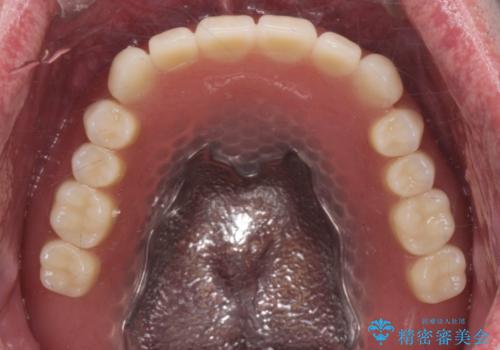

適合もよくしっかり噛めるようになりました。

見た目も改善されてとても満足して頂けました。